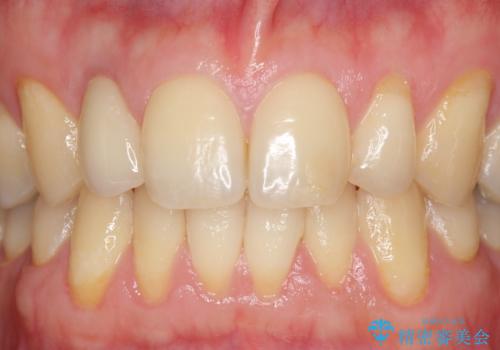

- 金属を使っていない被せ物に替えたいといらっしゃった方の症例です。

再根管治療終了後、オールセラミッククラウンによる補綴を行いました。

今回用いたオールセラミッククラウンはジルコニアフレームという白い素材の上にセラミックを盛っているため、審美性が非常に高いのが特徴です。

また、ジルコニアは人工ダイヤモンドの材料にも使われているほど高い強度を持っており、そのためオールセラミッククラウンは審美性だけでなく、奥歯やブリッジの補綴も可能とするクラウンです。